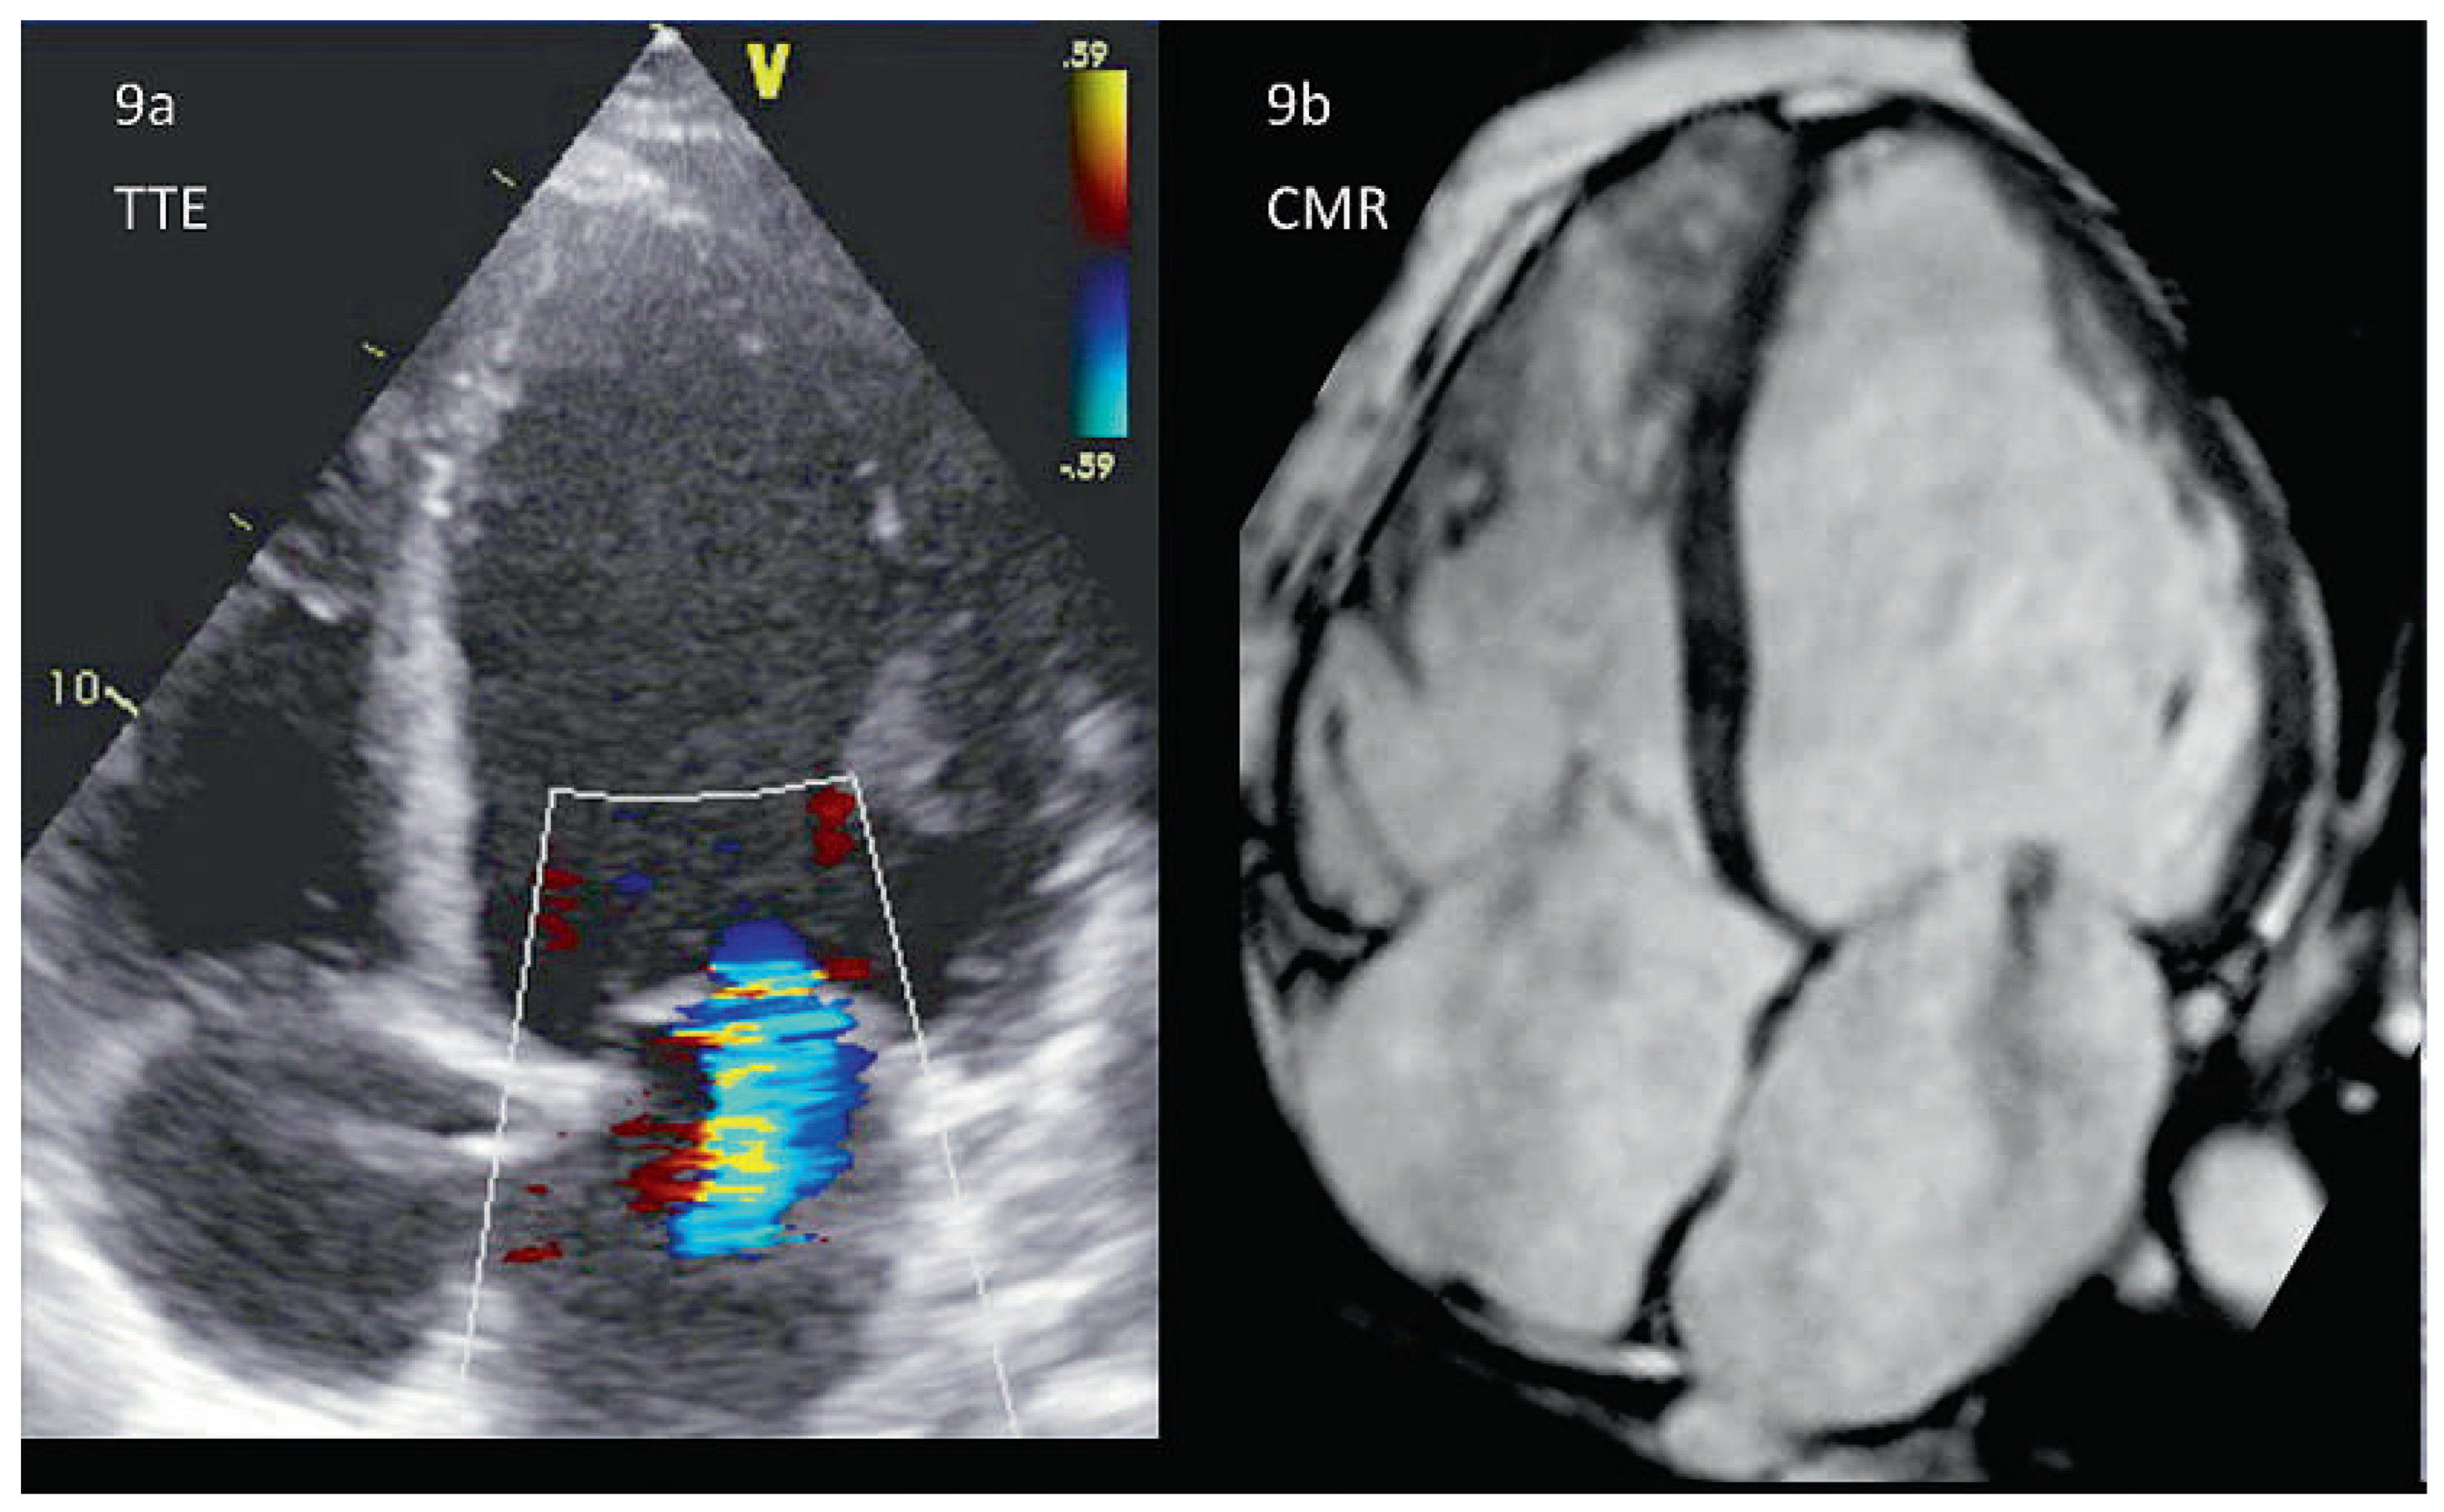

Abbildung 11. Mitralklappenstenose bei verkalkten Segeln im CMR, CT und TTE (identischer Patient). 11a: Die CMR ist zur Darstellung von Verkalkungen wenig geeignet, zeigt aber ähnlich wie die Farb-Doppler Echokardiographie (11d) die Flussbeschleunigung über der stenotischen Klappe gut. Abb. 11b: Im CT lassen sich die verkalkten Strukturen präzise vom umliegenden Gewebe abgrenzen. Abb. 11c/d: Diese Verkalkungen sind auch in der Echokardiographie gut darstellbar. Die gleiche Darstellung ist aber selbst beim identischen Patienten eine Herausforderung.

Wenn ausgeprägte Verkalkungen das Bild der gemischten Mitralinsuffizienz beherrschen, so kann die Qualität der transthorakalen Echokardiographie massgebend beeinträchtigt sein. Das kann bis hin zur völligen Verkennung einer Mitralinsuffizienz im Schallschatten des verkalkten Anulus reichen. Hier ist bei klinischer Symptomatik eine transesophageale Echokardiographie, ggf. auch eine CM- Roder CT-Untersuchung zu erwägen (Abbildung 11). Speziell die CT ist eine hervorragende Modalität zur Darstellung der Verkalkungen, die exakte Lokalisation der Verkalkung hilft bei der operativen Planung (Resektion bzw. Rekonstruktion des Anulus) [49]. Bei weniger ausgeprägten Veränderungen hingegen stellt die TTE oder TEE das subtile Zusammenspiel zwischen Kalk, Fibrose, Segelverdickung und -beweglichkeit oft sehr genau dar – eine notwendige Voraussetzung, um die exakte Regurgitationsursache zu definieren und eine geeignete Therapie abzuleiten. Die geringe zeitliche Auflösung limitiert hier insbesondere den Einsatz der CT. Die vor allem diastolisch aufgenommenen Bilder können dazu führen, dass ein Mitralklappenprolaps übersehen wird. Infolge der geringen zeitlichen Auflösung können zudem Verdickungen oder Tumore als Ursache einer Mitralinsuffizienz in der CT verpasst werden (Abbildung 12).